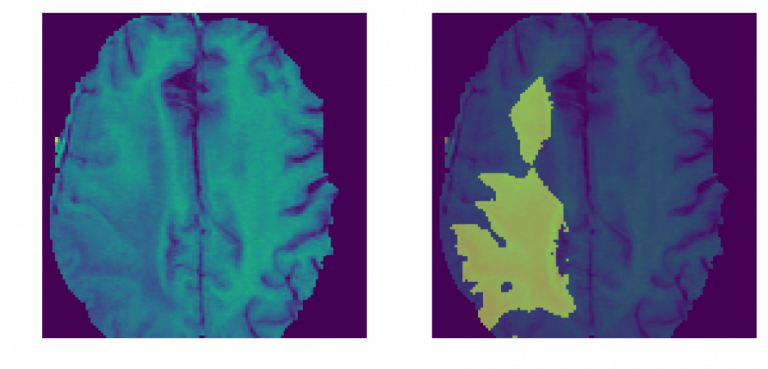

Trong y tế, cách gán label trên áp dụng như sau

Bác sĩ nhìn vào “bản đồ màu” này sẽ biết ngay diện tích khối u chiếm bao nhiêu phần trăm diện tích não mà không cần phải tự mình dùng mắt thường để đo đạc từng li một trên ảnh đen trắng mờ ảo

Tóm lại, Semantic Segmentation giống như dùng bút màu highlight chỗ quan trọng trong văn bản, mở lên phát biết ngay chỗ nào cần để ý